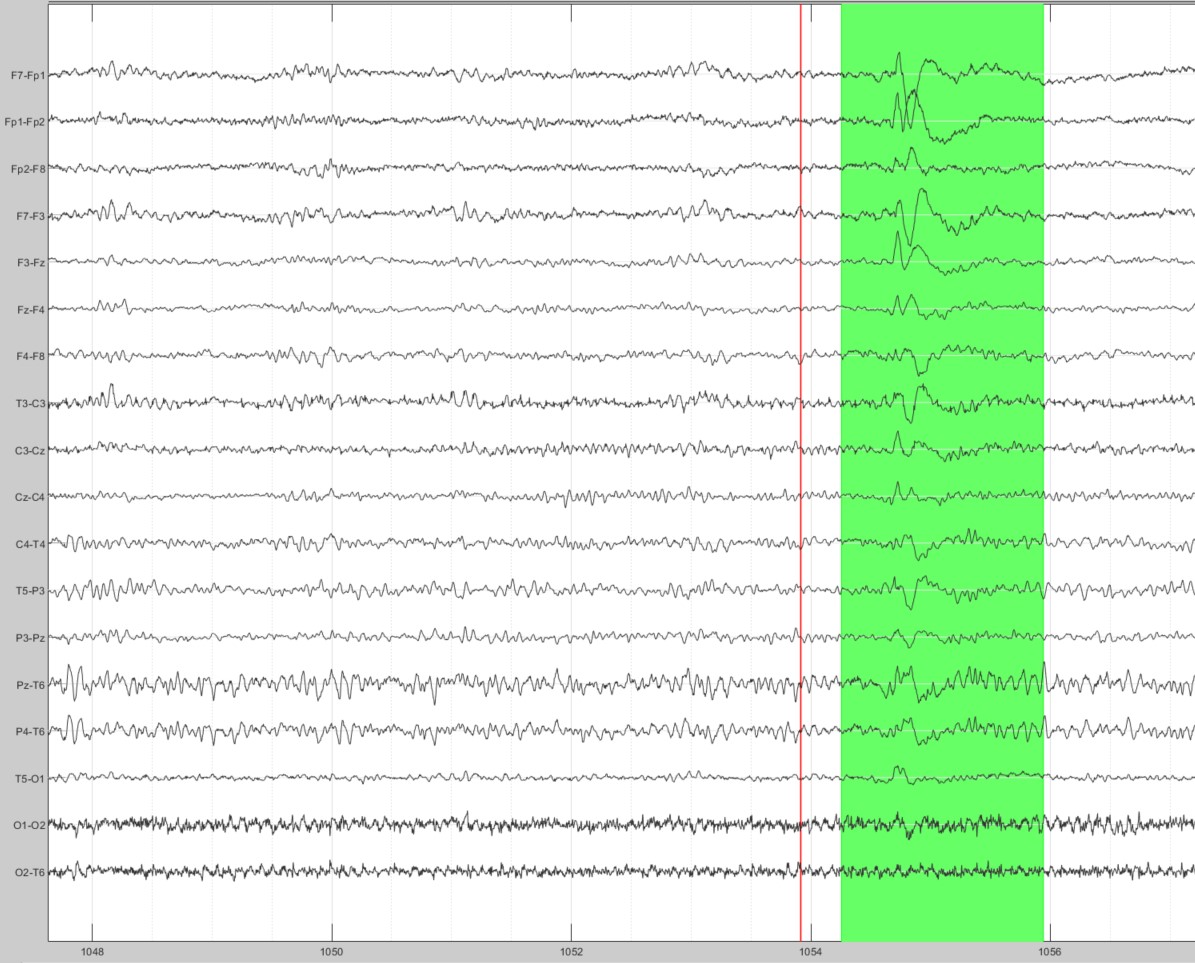

I wanted to ask the experts here if power can be calculated on such brief segment of generalised spike/wave. In the 30 minute recording this subject had only this single spike. Can a peak PSD be reliably calculated for such a brief segment and if so what window size and taper should ideally be used. I am using 4 second windows for other subjects who have 2 or more cycles of the spike/slow wave. I am not really interested in time-resolved frequency band. Just the freq-power relationship. This is quite confusing for me. All help will be highly appreciated.

Name: Screenshot 2021-03-04 160610.jpg